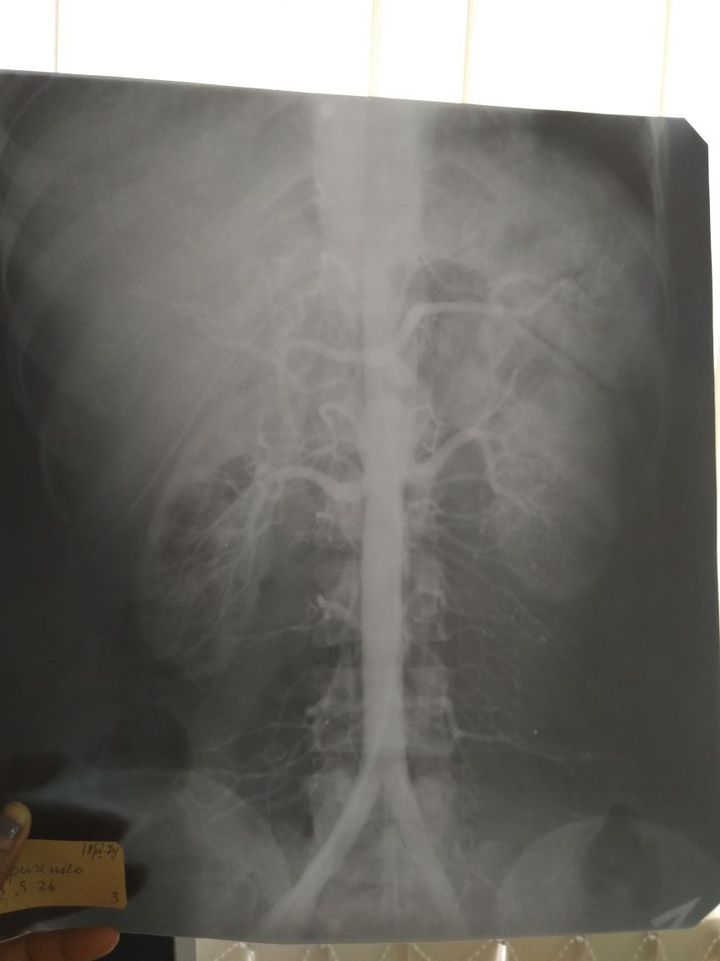

Please diagnose

AAA

Double kedney

Where the double kidney It is under the diaphragm and I think there also kidney closed to empric ??!

Abdominal aortic aneurysm